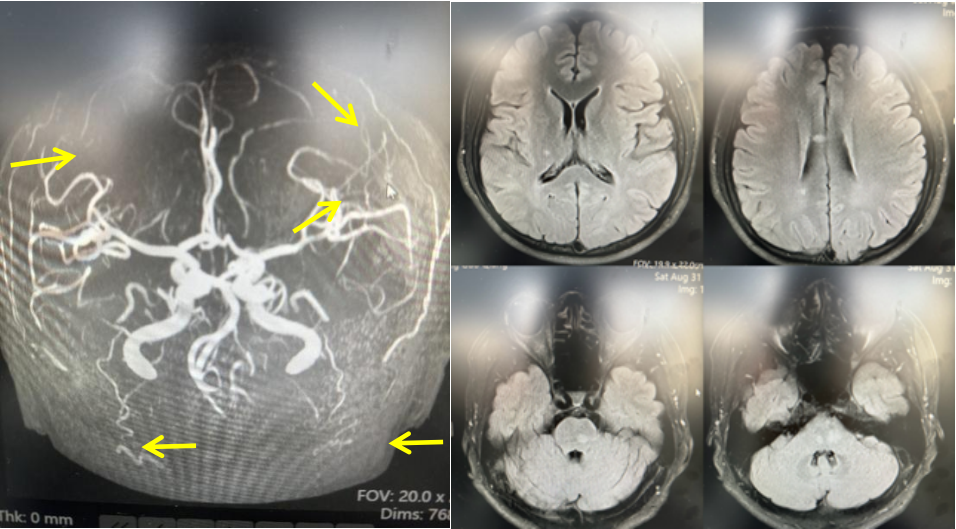

颅脑MRI平扫示右侧胼胝体体部、右侧侧脑室旁、右侧顶叶及桥脑多发异常信号;颅脑MRA未见明显特异性改变。(黄色箭头所示)